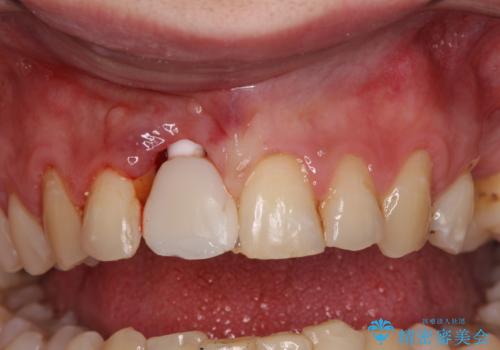

首の皮一枚で繋がっている前歯 1DAYインプラントでスムーズに治療

- 外れるたびに接着剤で応急処置を施してきた前歯のインプラント治療を希望して来院された患者様です。

以前から治療が必要であることは認識されていましたが、海外から日本に移住された1週間後に前歯が脱離したことで、当院でのインプラント治療を選択されました。

度重なる脱離により、表側の炎症が非常に強くなっており、歯を支える骨が失われている状態でした。

そのため、現在の位置よりも歯と歯肉の位置が退縮する方向に移動する可能性があり、前歯2本の歯肉位置が大きくずれることとなるため、本人との相談のうえ、天然歯が萌えているような歯肉状態とはならないものの、2本の段差が少ない状態にて治療を終えることとなりました。